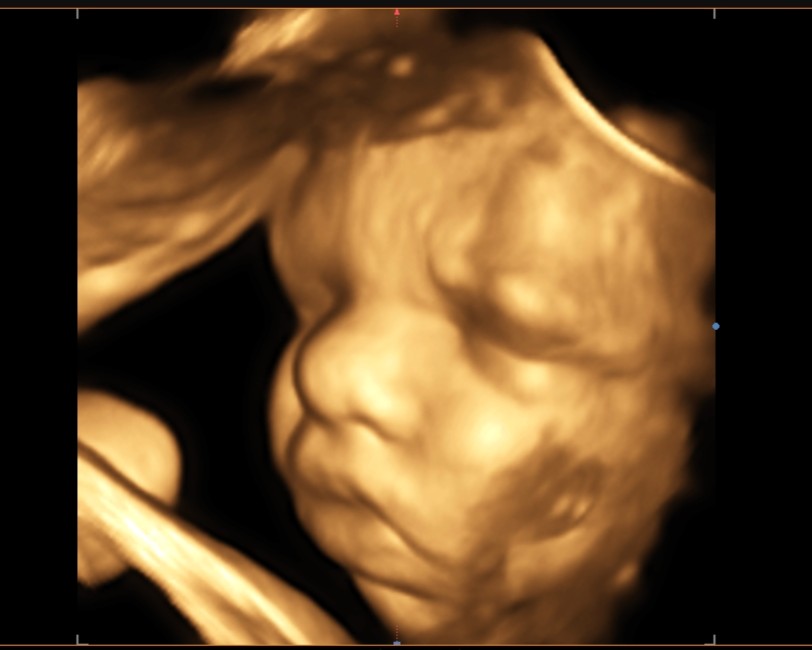

Ultrazvuky umožňují i dopplerovská měření a 3D-4D zobrazení

• Provádíme 3D-4D zobrazení (vzhledem k časové náročnosti si pacientky objednáváme mimo ordinační dobu).